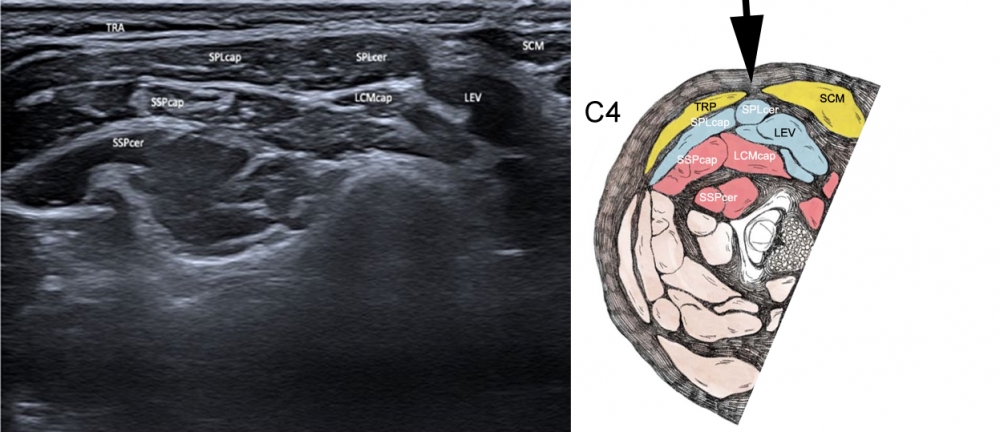

Ultrasound-Anatomical correlation

Figure 2. Ultrasound at level of C4. Approach indicated by black arrow.